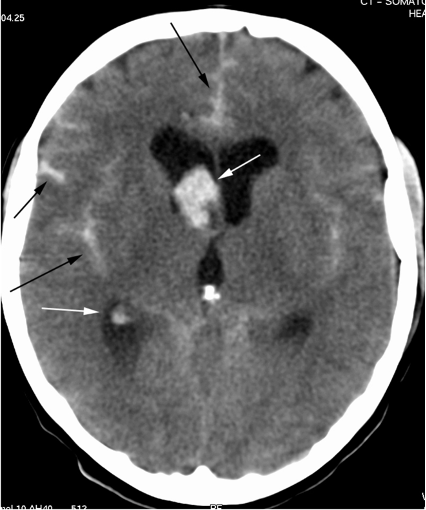

Q

Diagnose?

A

Subarachnoidalblødning (SAH)

Intracerebral hæmoragi (ICH)